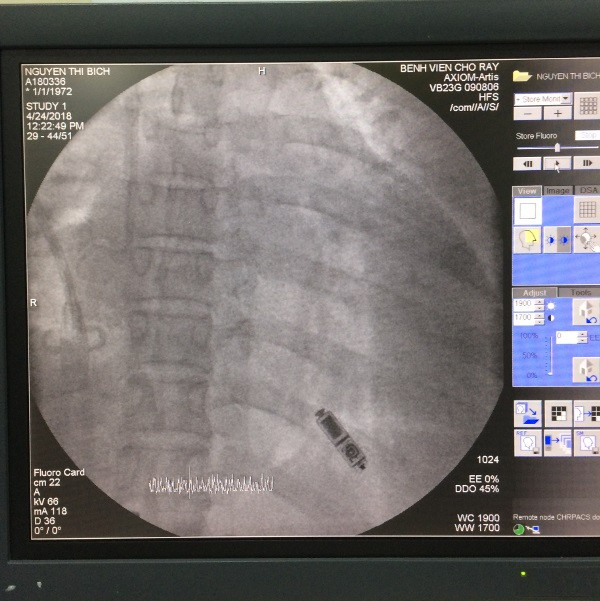

Bệnh viện Chợ Rẫy đặt máy tạo nhịp tim không dây thành công ảnh 3Sau khi đặt máy tạo nhịp tim

Sau khi hội chẩn, các bác sĩ xác định không thể đưa được dây tạo nhịp vào tim phải theo đường thông thường, do BN chạy thận lâu ngày đã làm thay đổi đường đi của mạch máu. Khoa Điều trị Rối loạn nhịp BV Chợ Rẫy đã tiến hành hội chẩn từ xa với PGS.TS Sirin Apiyasawat (Phó chủ nhiệm khoa Y, Phó giáo sư phân ngành tim mạch khoa Y BV Ramathibodi Thái Lan) và thống nhất sẽ tiến hành đặt máy tạo nhịp tim không dây cho BN.

Đây là loại máy có kích thước rất nhỏ nằm toàn bộ trong buồng thất phải của BN, được đưa vào trong buồng thất phải bằng ống thông từ tĩnh mạch đùi. Máy có dạng hình trụ tròn, tổng trọng lượng của máy là 1gam. Máy cho phép tạo nhịp tim cho người bệnh trong thời gian từ 8-10 năm.